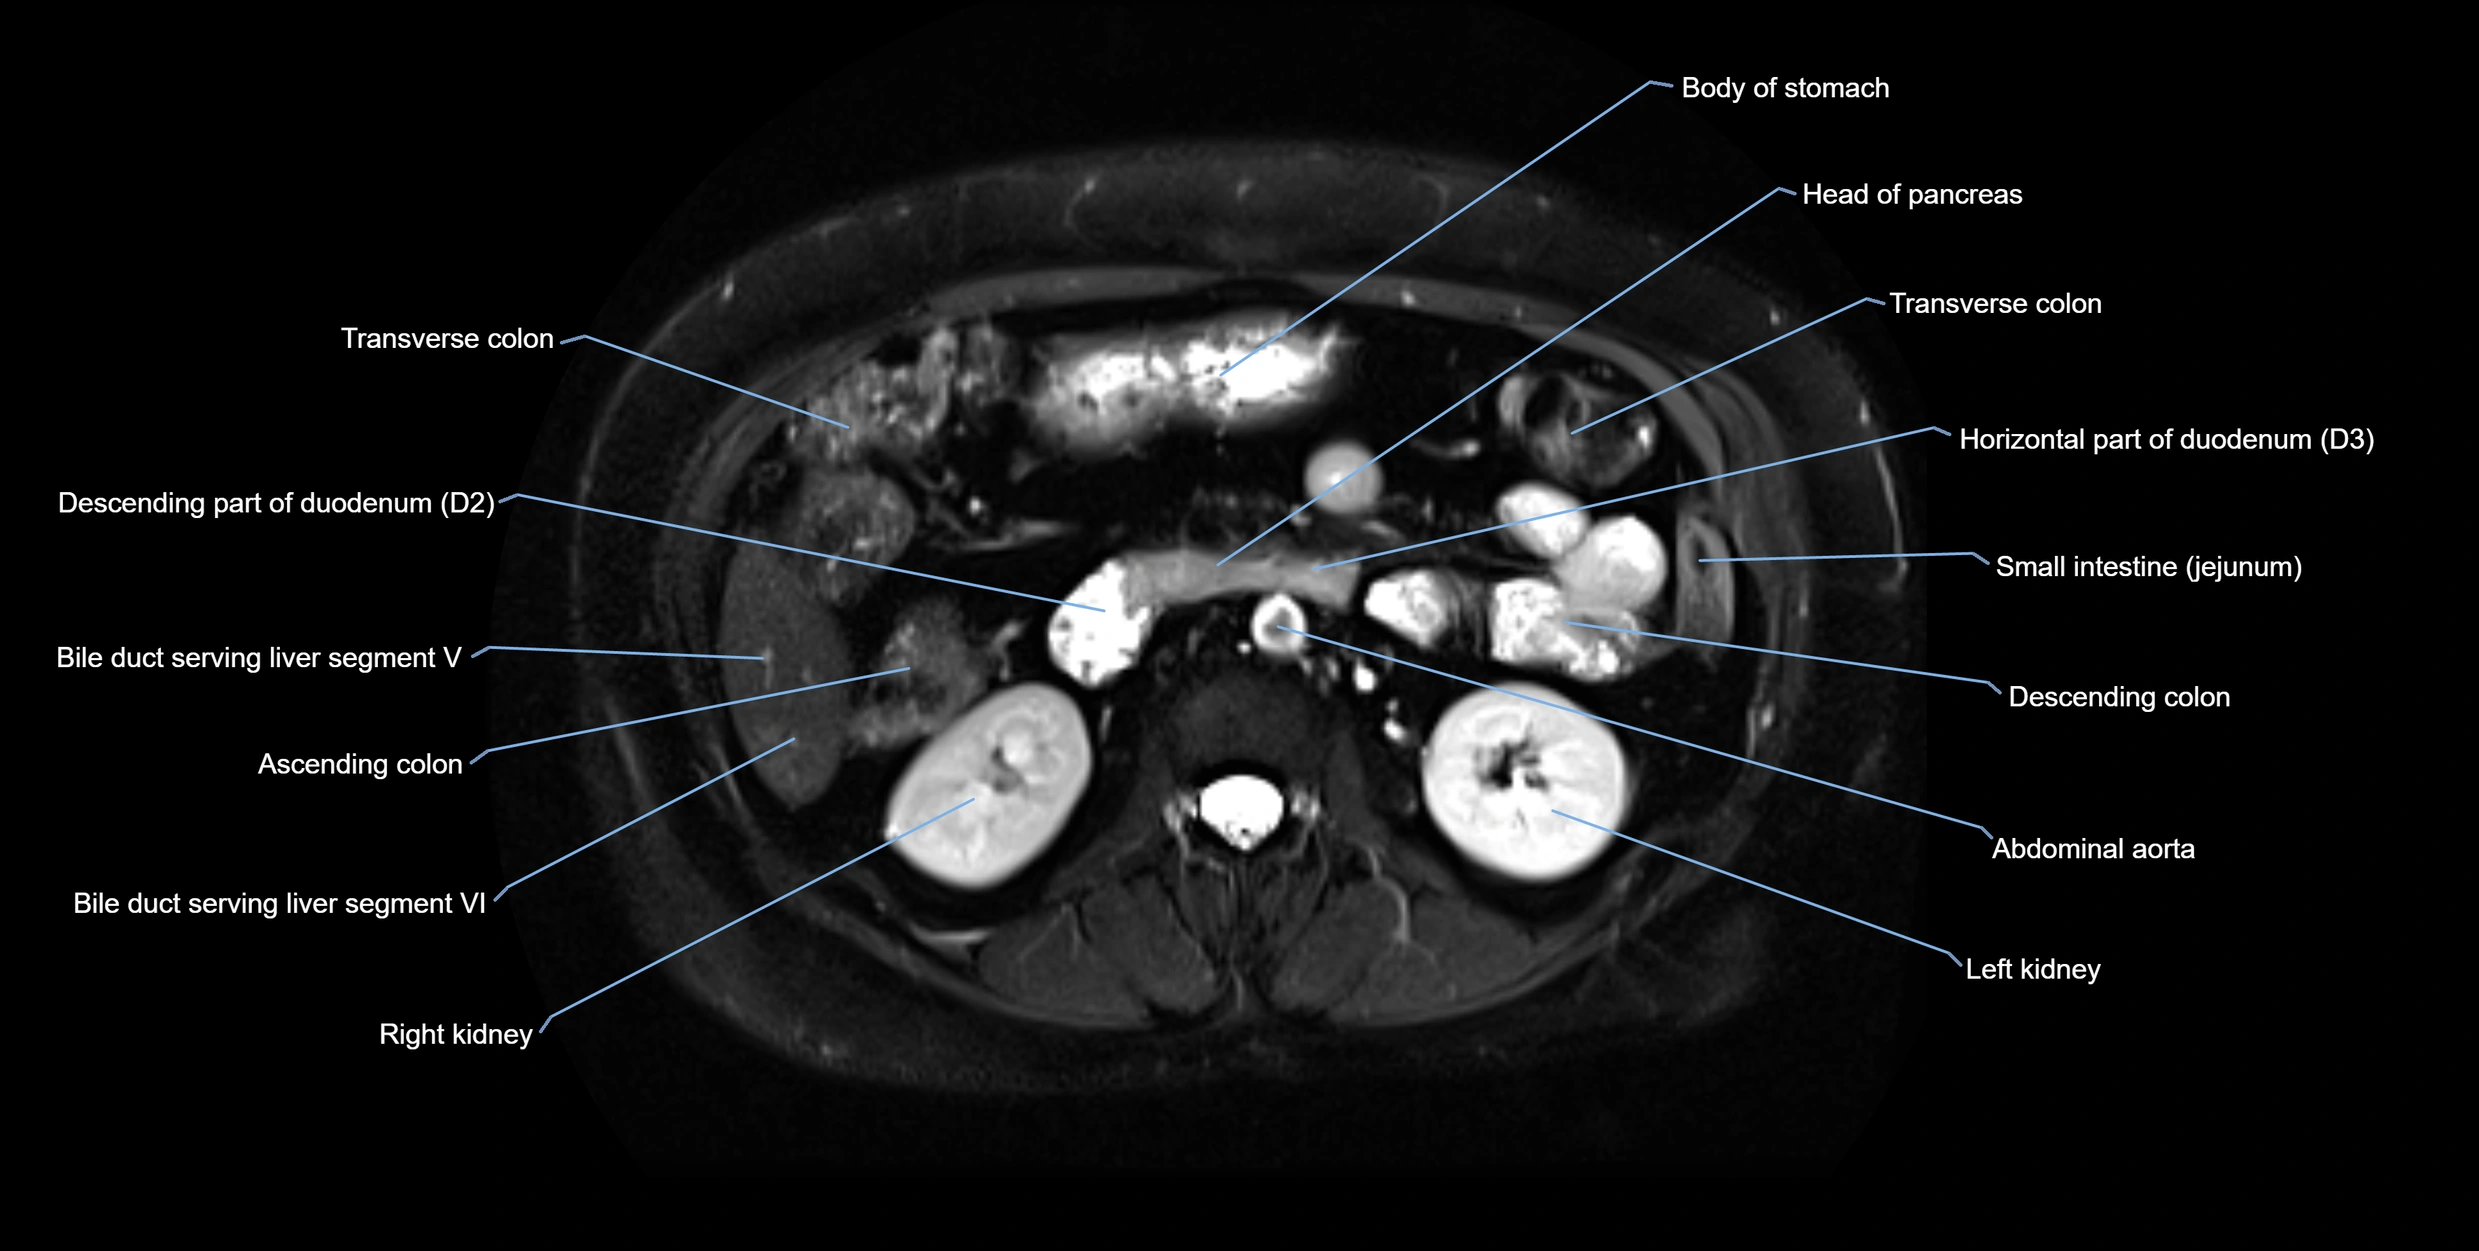

T2-weighted images:

• Duct fluid appears bright

• Accessory duct seen as a fine high-signal tubular structure in pancreatic head

T2 Fat-Saturated HASTE (single-shot):

• Accessory duct: bright, thin linear structure in pancreatic head

• Stones, strictures, or air bubbles appear as dark filling defects

• Excellent for rapid evaluation of duct patency

T2 TSE Fat-Saturated 3D (MRCP sequence):

• Duct visualized as a continuous bright tubular structure joining or parallel to the main pancreatic duct

• Allows 3D reconstruction of ductal anatomy and variants

• Excellent for diagnosis of pancreas divisum

MRI image

image